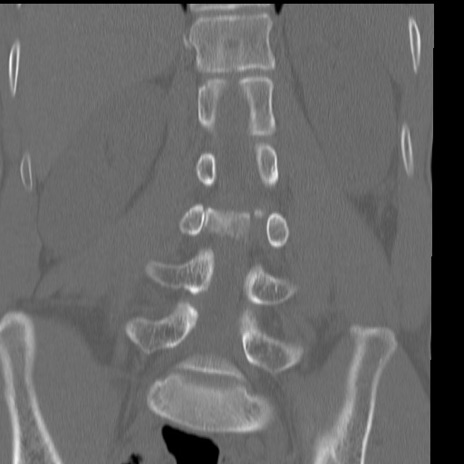

症例3 腰椎CT(冠状断像)

腰椎CT